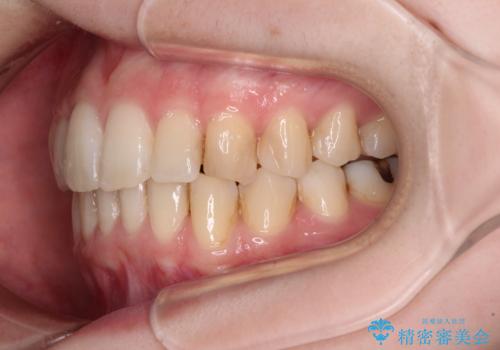

左右ともに奥歯の咬み合わせには大きな問題がなく、窮屈な歯列を解決すれば歯列を整えることできたため、僅か1年で終えることができました。